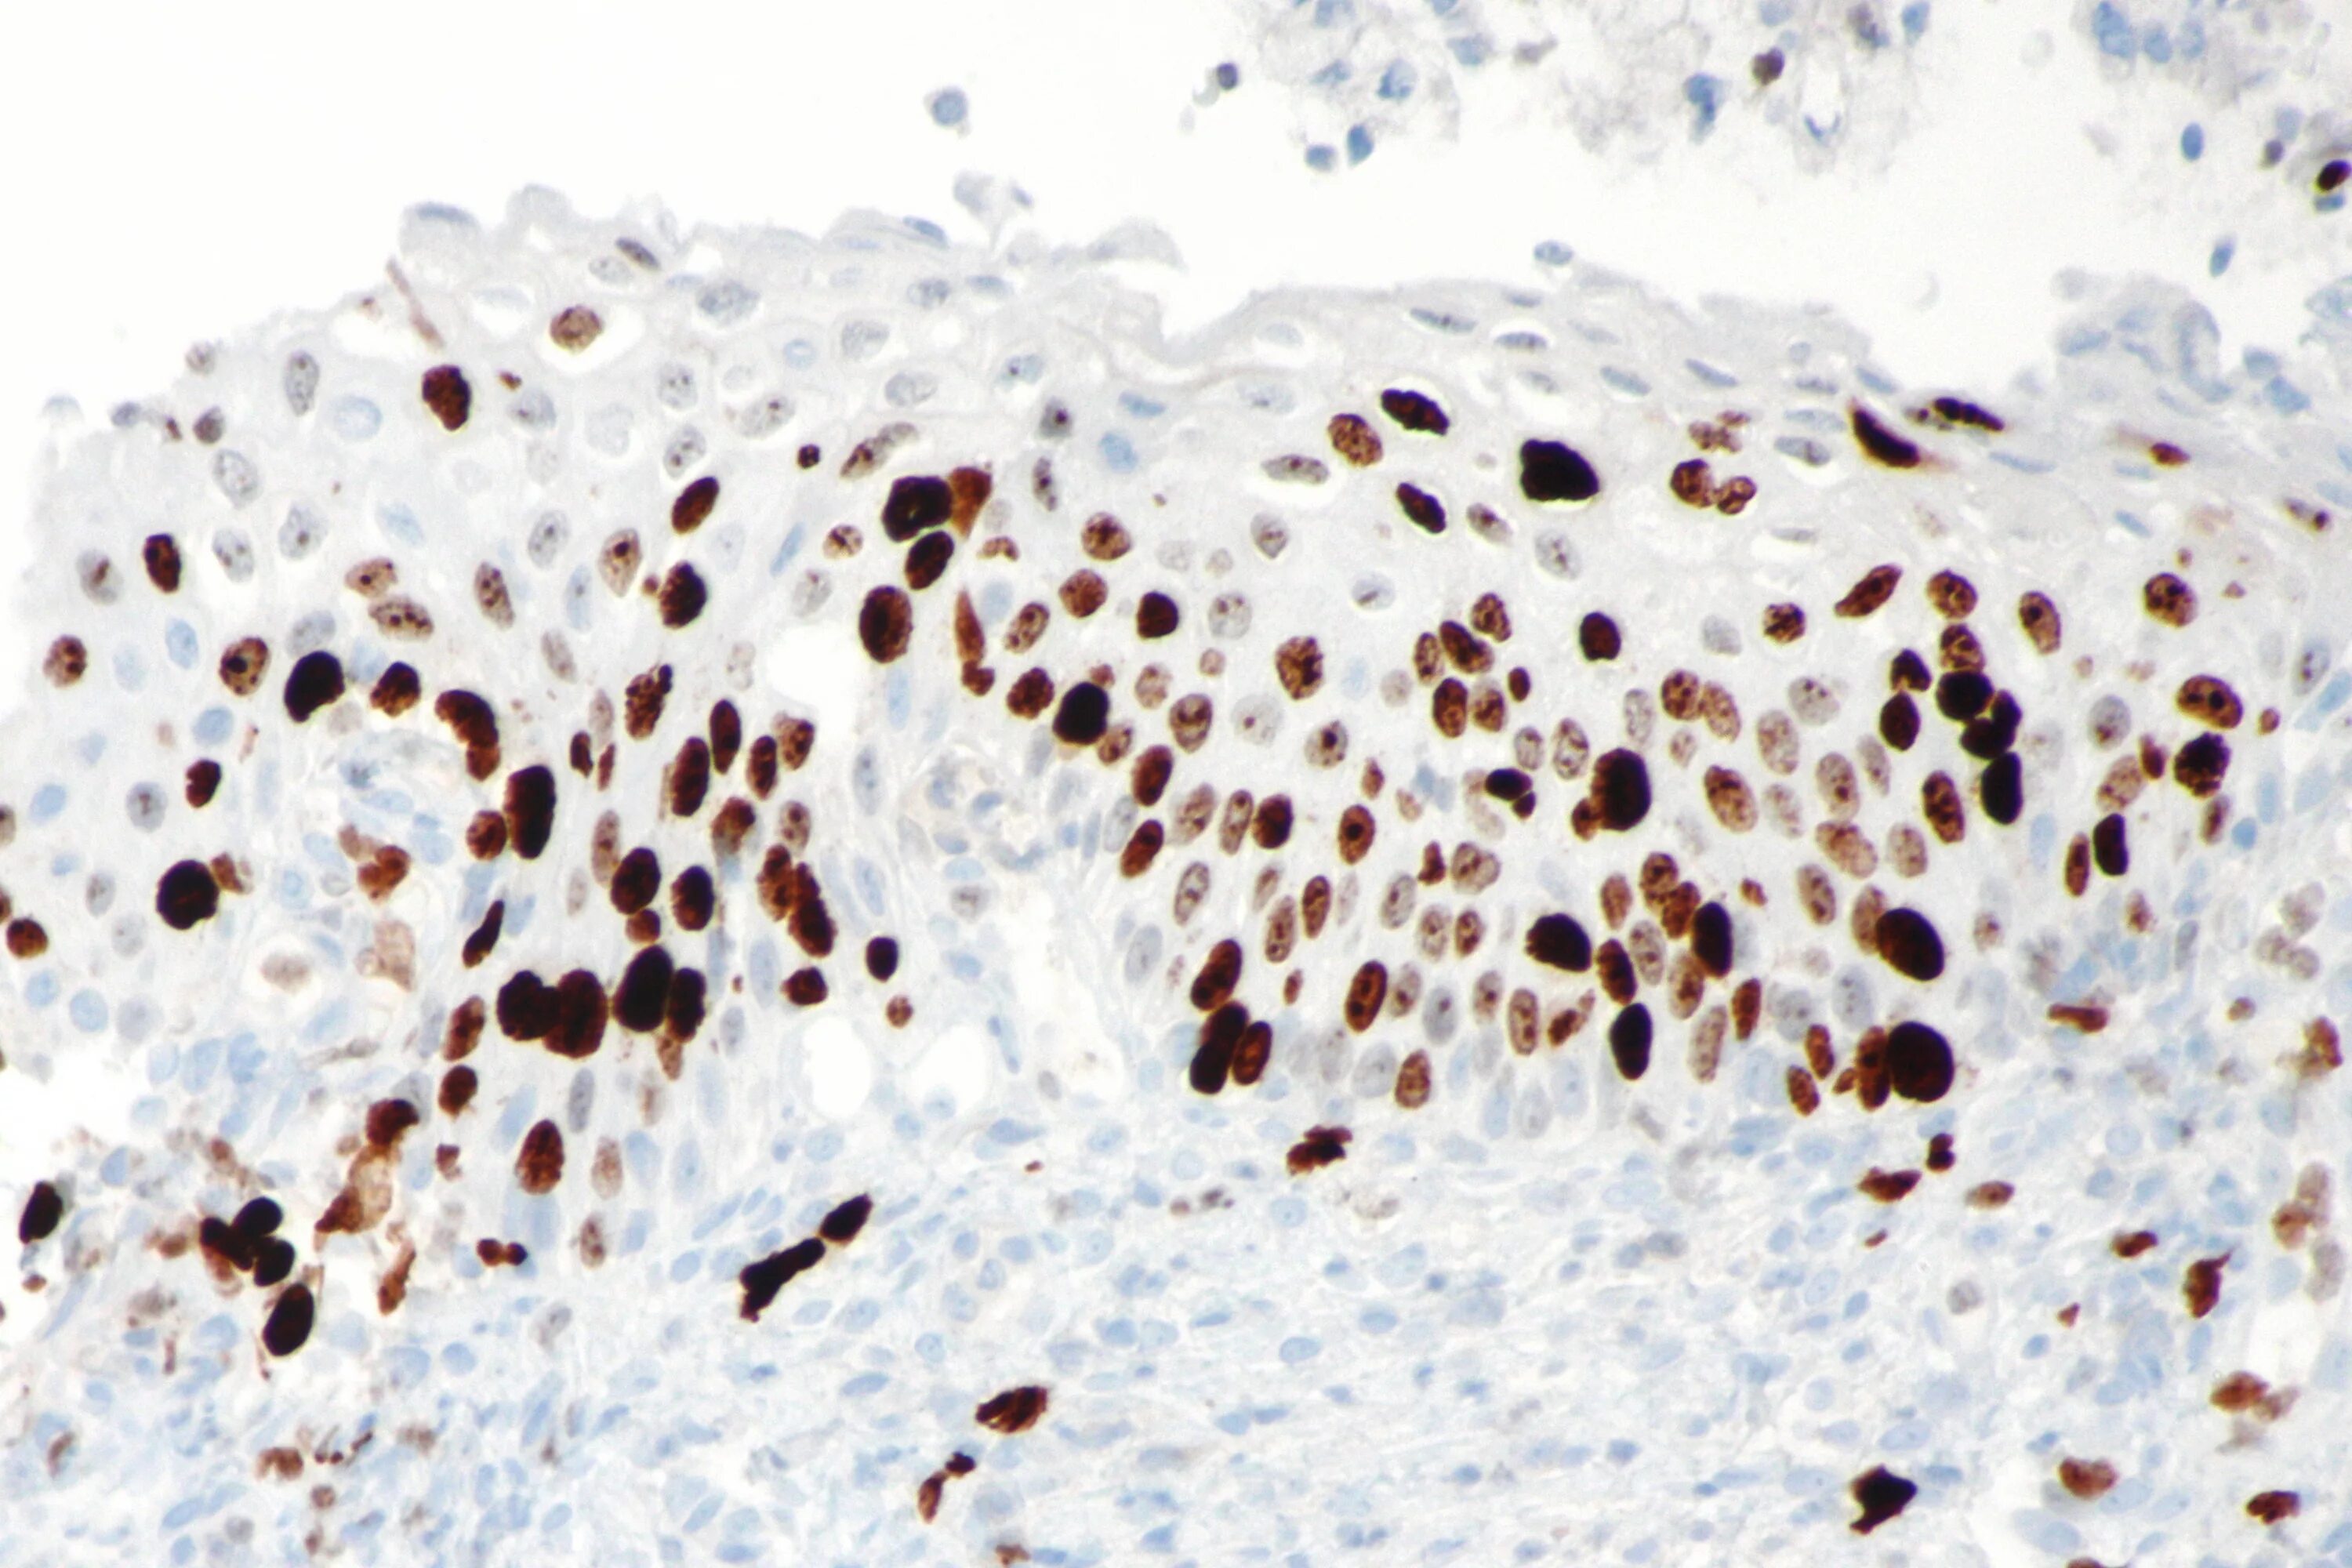

Кал методом игх спб